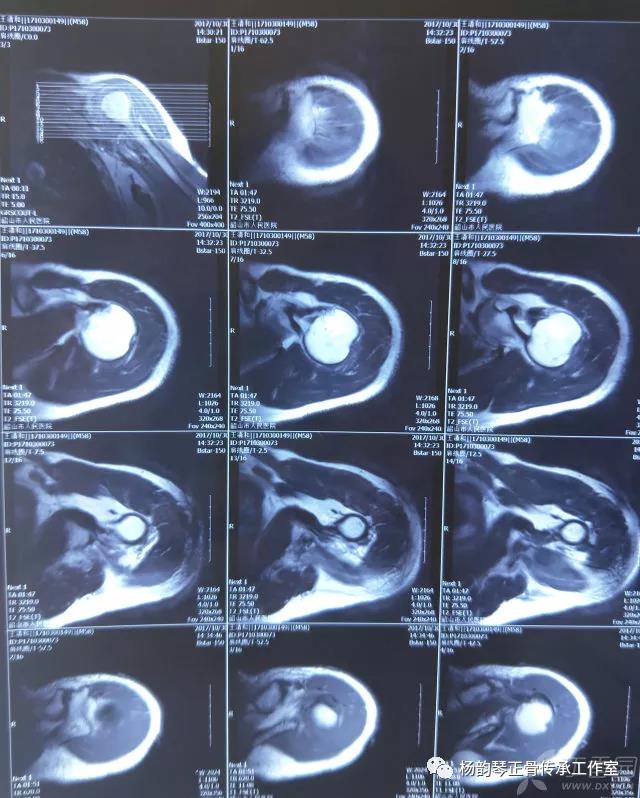

简要病史:骑摩托车跌倒致左肩部肿痛,活动受限,就诊于当地医院,拍片及磁共振检查后诊断为肩袖损伤及肩关节半脱位,予以悬吊固定,因症状缓解不明显就诊于我院。外院拍片情况如下:

应该说是一个典型的“灯泡征”影像,但是并未引起注意。

磁共振检查也完善了,还是报了个肩关节半脱位……影像科已经把坑挖好了……